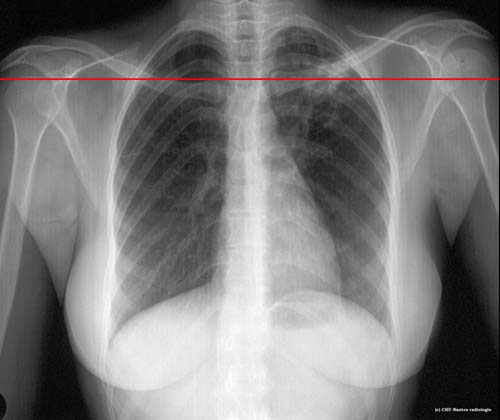

Lésions cavitaires : niveau de la coupe TDM